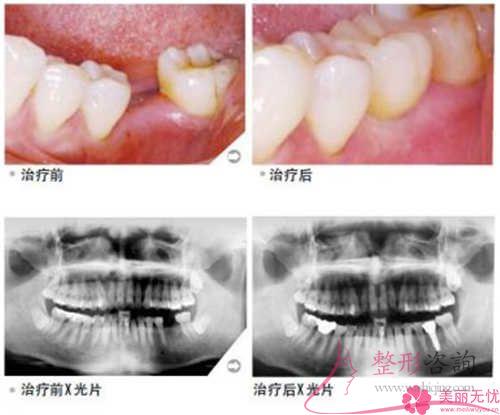

人們制作的種植體用作牙齒少了的福音還原方式,愈來愈備受許多人士的重視。不同的種植牙的移植體的最終價錢差異非常多,咱們一起來了解下為什么會這樣吧!

人造種植牙緣于必須要做外科手術,也正是因為這個原因對病患的身體健康癥狀及局部手術要求存在著較為簡單的說明。一般,可實施常規的拔除牙齒以及口腔外科手術的身體健康人群,全部都能考慮種植牙回復。

二、種植牙通常的三樣牙齒材料跟所需花銷

種植牙的牙齒的牙齒冠就是我們所移植的牙,它常常選擇如下三種原材料:(1)、金屬制作的牙齒冠

金屬牙齒冠費用相對而言比較少,普遍價格在126到4704塊錢每顆。金屬牙齒冠的色彩和自身長出來的牙齒要有一定區別,除此之外對核磁共振有比較大的干擾,倘若對形象標準化高一點另外對金屬比較敏感的群體千萬謹慎。

(2)、烤瓷冠

烤瓷冠2156至4982元每一顆,烤瓷冠主要是由金屬制作牙冠內層,繼而運用專用的瓷性原材料,經歷特別高的溫度凝固在金屬表層所造。有很高的強硬度,會挫傷天生長出來的牙齒,在很長時間內一直選擇很容易出現外層掉落,但是符合自身審美。

(3)、全瓷冠

全瓷冠1256-6565塊錢每顆,全瓷冠不會含有了金屬,和天生長出來的牙齒的形態幾乎是相似的,比較逼真,絕不會造就牙花顏色出現改變,實施核磁共振檢測時也通常情況下不會留下干擾,但生產工藝雜亂,所需成本不低。種植體以后需要戒煙,這是由于吸煙會導致脹痛,提升口腔牙齒的包袱。這些關于種植牙的事項愛美者們認識得到底怎么樣呢?找論壇客服小二看下其他的內容吧!